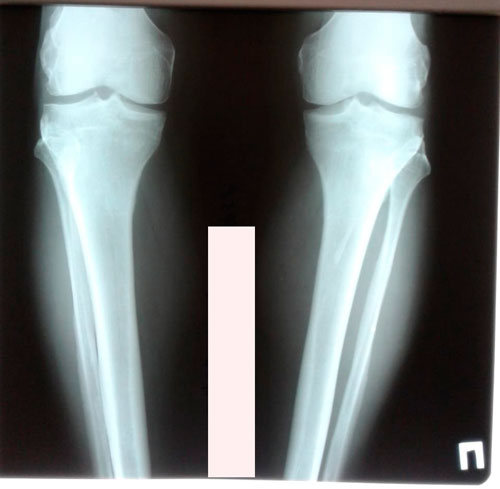

Исходник - 60 лет.

Дата операции - 11.04.2019.

IMG_2331-11-04-19-11-12.JPG

IMG_2336-11-04-19-11-12.JPG